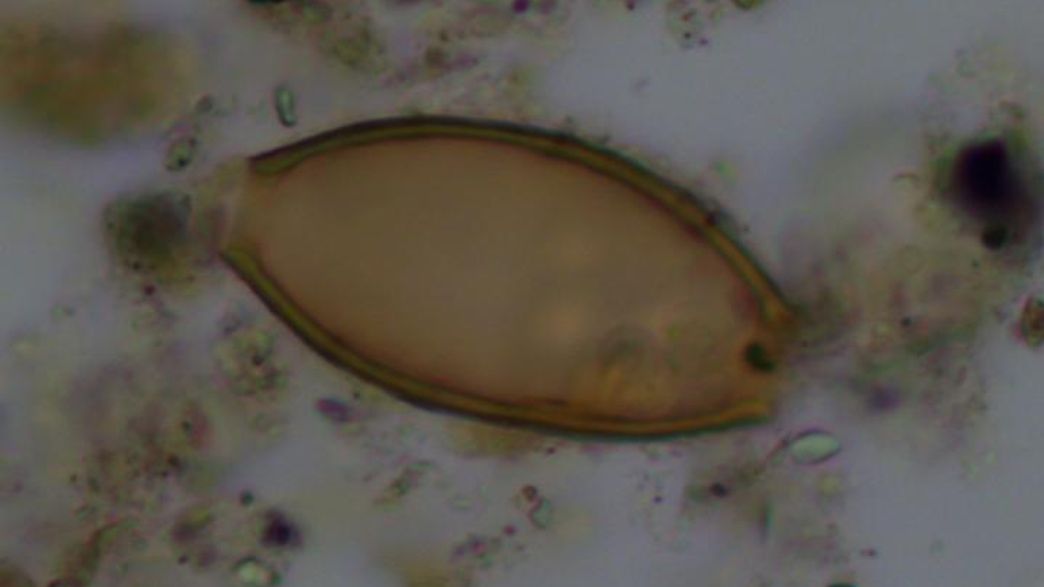

Poop Proof Ancient Greeks Suffered from Gut Parasites Live Science Poop Greek Etymology The word manure itself has its origins in nothing at all to do with excrement: It is also recorded as a verb from the middle english period. “poop” came into its current meaning around 1900. The word “poop” comes from the onomatopoeia poupen or popen, which originally meant “fart”. The roots are latin words for “hand” and “work,” and the. Poop Greek Etymology.